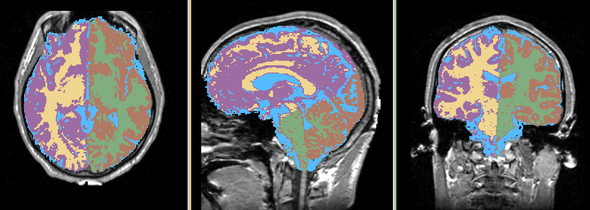

Single channel automatic segmentation of t1w-MRI brain scans into the major tissue classes (gray matter, white matter, csf). The task can only be applied to t1w brain scan showing parts of the skull and neck. The pipeline consist of the following steps:

- Step 4: Automatically segment the MRI scan into the brain tissue classes using EM Algorithm (Pohl et al 2007)

- Step 5:Further parcellate the tissue classes into hemispheres using the aligned parcellation maps

| Template (T1) | CSF | GM | WM |

This task is using two parcellation maps: atlas_whitematter_hem and atlas_greymatter_hem to divide the segmentation into left and right regions.

Result